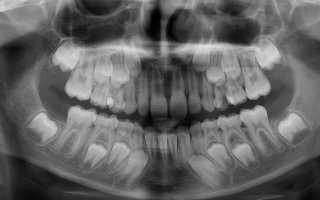

У вас остался молочный зуб, а вы не знаете, что делать? Обязательно покажитесь стоматологу. Переживать по поводу того, что молочная единичка будет сразу удалена, не стоит – удалять ее прямо сейчас или нет, врач будет решать только на основании рентгенологического исследования.

Рассмотрим, по каким критериям будет приниматься решение.

1. Оценка состояния молочной единицы

Здесь важно обратить внимание на состояние корней и определить, не подвергаются ли они резорбции, т.е. рассасыванию. Также важно учесть, устойчив ли зуб и не расшатывается ли он – если он крепко держится в лунке, неподвижен, не поражен кариесом или иными заболеваниями, не разрушен более, чем на 30%, то удалять его нецелесообразно. Его оставляют служить, пока он не разрушится, а, как показывает практика, такой зуб может сохраняться вплоть до весьма почтенных лет. Особенно если постоянный и не вырос на его месте совсем.

2. Определение наличия зачатков постоянных единиц

Врачу нужно понять и оценить следующие критерии:

- есть ли зачатки непрорезавшихся зубов в принципе,

- как располагаются зачатки относительно молочного зуба и на каком расстоянии,

- при каких обстоятельствах зачатки могут прорезаться,

- мешает ли прорезыванию именно молочная единица или этот процесс связан с какими-то заболеваниями, патологиями организма (возможно, врач направит вас на всестороннее обследование к узкопрофильным специалистам).

Если зачатки есть и вероятность их прорезывания существует, то специалист предложит удалить молочный «рудимент» и заняться процессом «вытягивания» постоянного клыка, моляра, резца или прямоляра. Правда, как долго будет проходить этот процесс, ответить никто не может – все сугубо индивидуально.